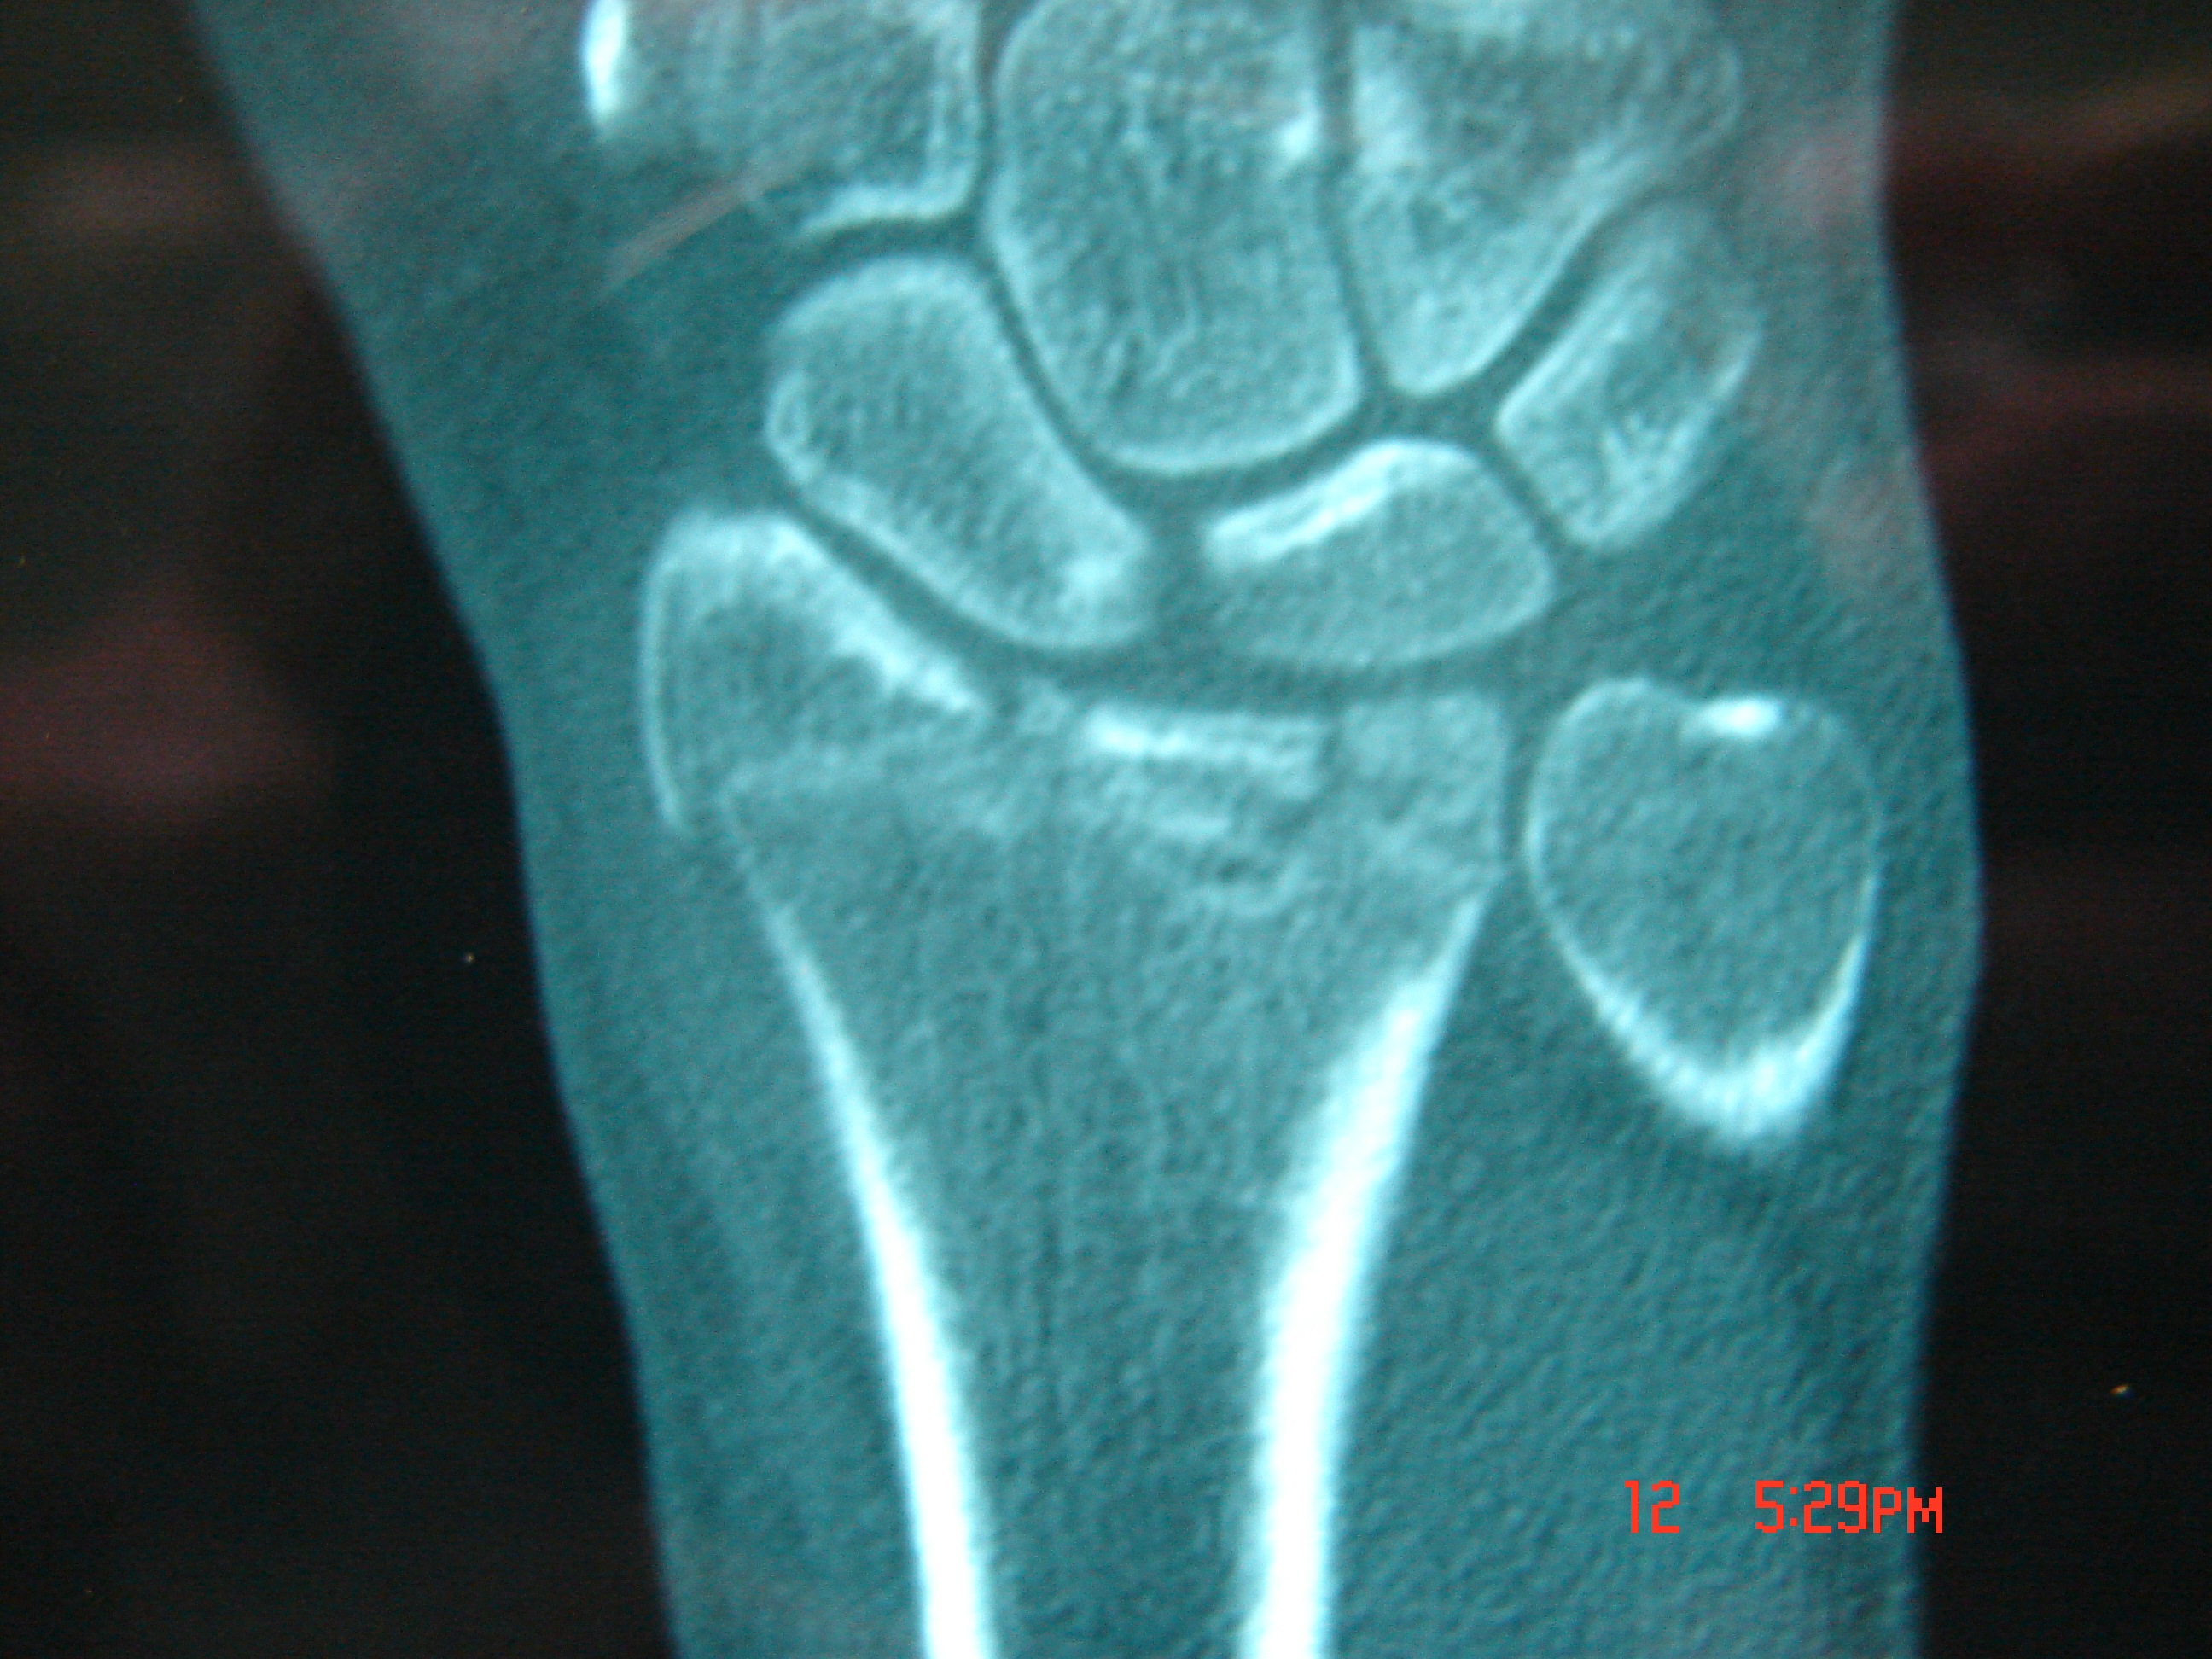

Εικόνα 4 α,β,γ

Συντριπτικό ενδο-αρθρικό κάταγμα με παρεκτόπιση

Το ενδοαρθρικό κάταγμα της πηχεοκαρπικής (κερκίδα) αντιμετωπίσθηκε συντηρητικά με πηχεοκαρπικό γύψο.